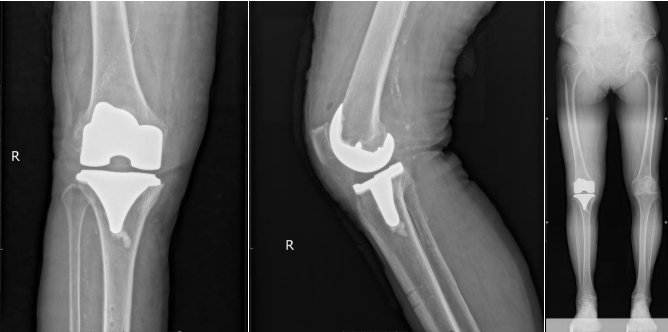

术后复查

机器人通过术前采集李婆婆下肢CT数据信息进行膝关节1:1三维模型重建,术前完成假体选择、截骨角度、截骨量等个性化数据设计,术中机械臂精准执行术前计划,并提供实时反馈及软组织保护,确保高精准度截骨并尽可能减少手术创伤,在一定程度上弥补了传统手术的不足。

一切准备就绪后,扶世杰教授带领暴丁溯博士、曾胜强等团队成员为李婆婆实施了机器人辅助全膝关节置换术,顺利完成手术。